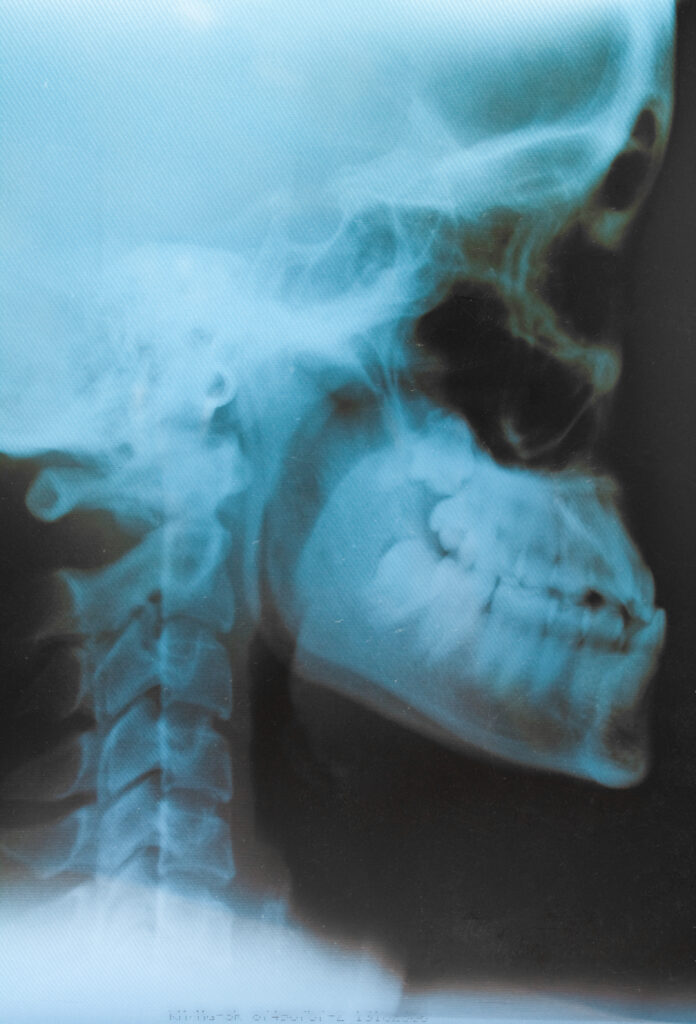

Stomatolog ma do dyspozycji wiele metod diagnostycznych – od badania klinicznego, przez analizę modeli zgryzowych, aż po zaawansowane badania obrazowe. Dzięki temu możliwe jest wczesne wykrycie nieprawidłowości i zaplanowanie leczenia dla przywrócenia prawidłowej okluzji.